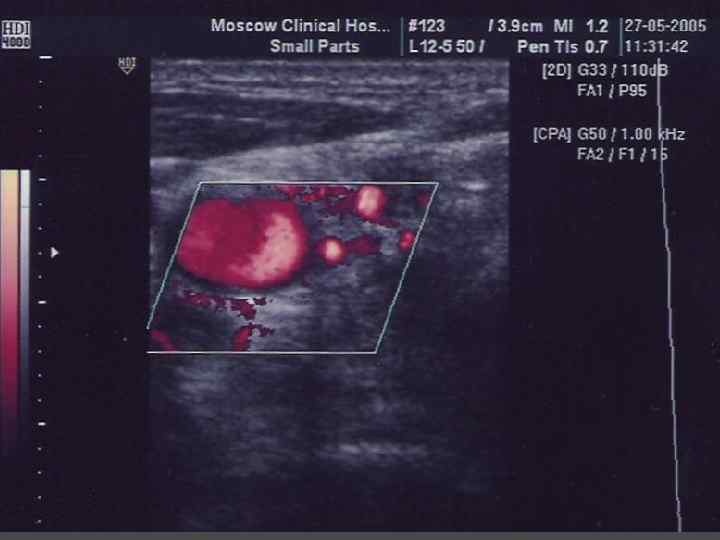

УЛЬТРАЗВУКОВОЕ ИССЛЕДОВАНИЕ